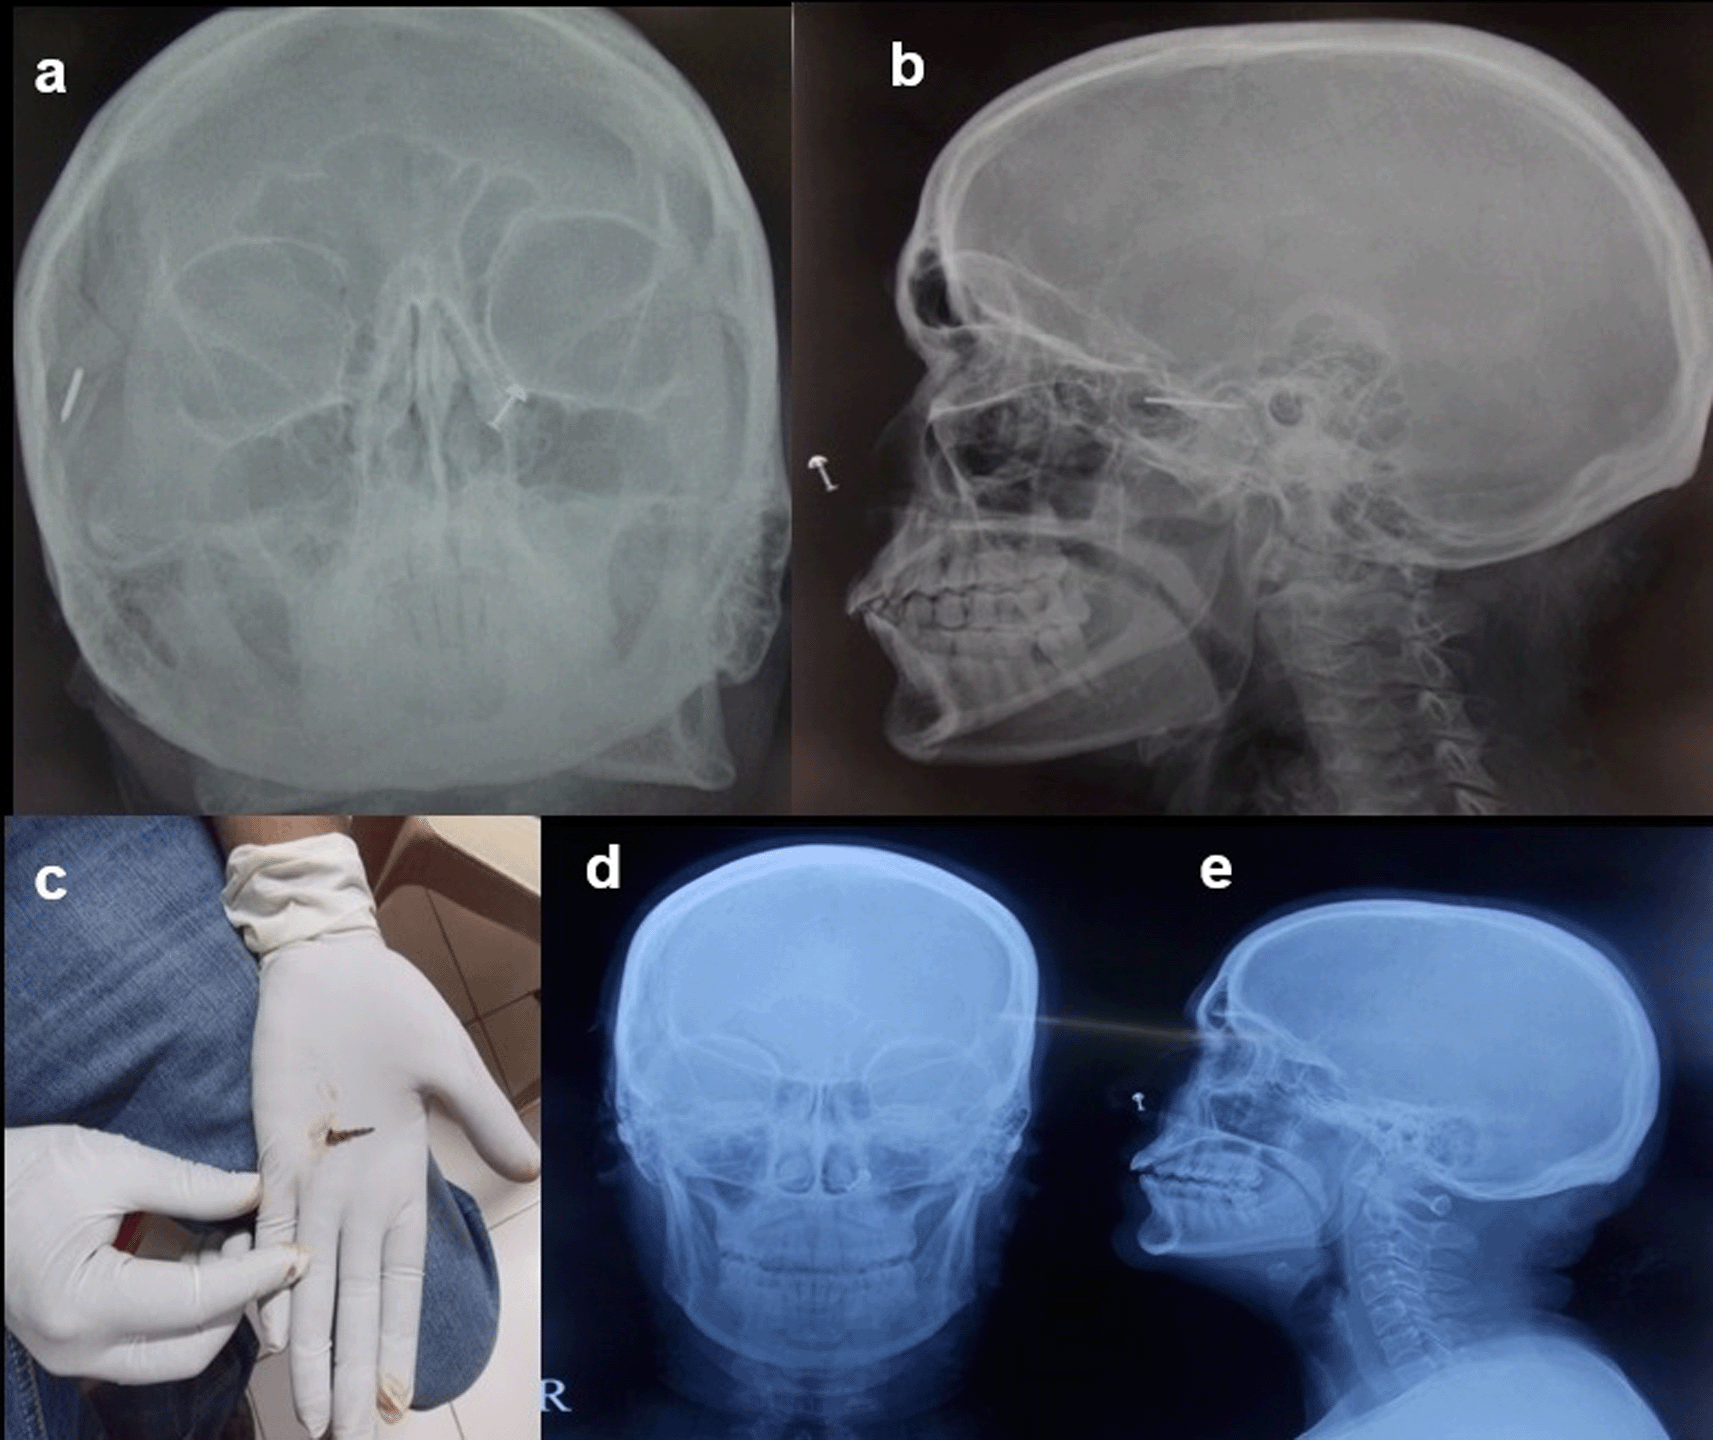

Case 8: A 50-year-old woman came for cervical spine. The patient complained of neck pain and headache for more than 1 year. The clinical examination was unremarkable. The patient was taken for an MRI scan when she complained of a severe headache. Radiograph skull AP & Lateral view was done, which showed a radiodense nail-like structure in scalp on right side. On asking, the patient gave a history of trauma ten years back and did not know that she had a nail in her scalp. It was removed under local anaesthesia.

Some metallic foreign bodies can be accidentally diagnosed during an MRI or CT study due to artefacts or sometimes due to pain as they enter the magnetic field12 (Figure 8a,b).

The nail removed under ultrasound guidance (c). Normal radiograph skull A-P & Lateral view post removal of the foreign body (d,e).